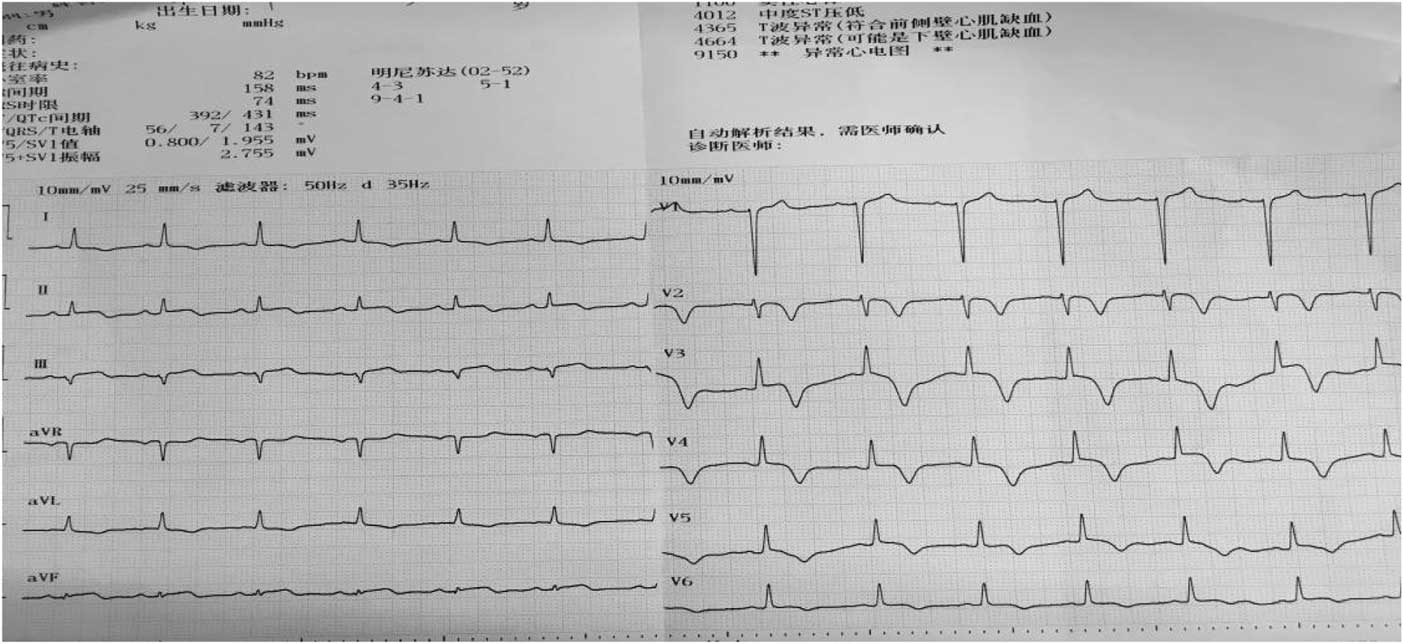

One day after the operation, his postoperative electrocardiogram showed that the elevated ST segments in II, III, aVF, and V4–V6 were down to baseline, and an inverted T wave began to appear in V2–V6 (Fig 4). An echocardiography performed 3 days after admission showed a left ventricular ejection fraction of 48.2%, enlarged bilateral atrium, dilated left ventricle, segmental weak pulse of left ventricular wall, mild regurgitation of bicuspid valve or of tricuspid valve, and the estranged left ventricular cells (Figs 5–7). Laboratory tests on the same day showed a higher troponin I of 31.833 ug/L, lower myoglobin of 27.9 ug/L, creatine kinase-MB of 21 U/L, creatine kinase of 74 U/L, and lactate dehydrogenase of 489 U/L. After 4 days, the serum laboratory results showed the following results: troponin I, 6.912 ug/L; myoglobin, 29.5 ug/L; creatine kinase-MB, 17 U/L; creatine kinase, 36 U/L; lactate dehydrogenase, 330 U/L; cholesterol, 2.86 mmol/L; low-density lipoprotein cholesterol, 1.63 mmol/L; triglyceride, 2.28 mmol/L; and high-density lipoprotein cholesterol, 0.57 mmol/L. All the related indexes were decreased. On the 14th day after the operation, the patient had a third examination of coronary arteriography, which revealed that there was barely any blockage caused by thrombi in the anterior descending branch and no stricture in the coronary artery (Figs 8 and 9). The patient was discharged on the 17th day, as his vitals were stable and symptoms disappeared.

Figure 4 Electrocardiogram on 1 day after operation shows that the elevated ST segments in II, III, aVF, and V4–V6 were down to baseline, and an inverted T wave began to appear in V2–V6.